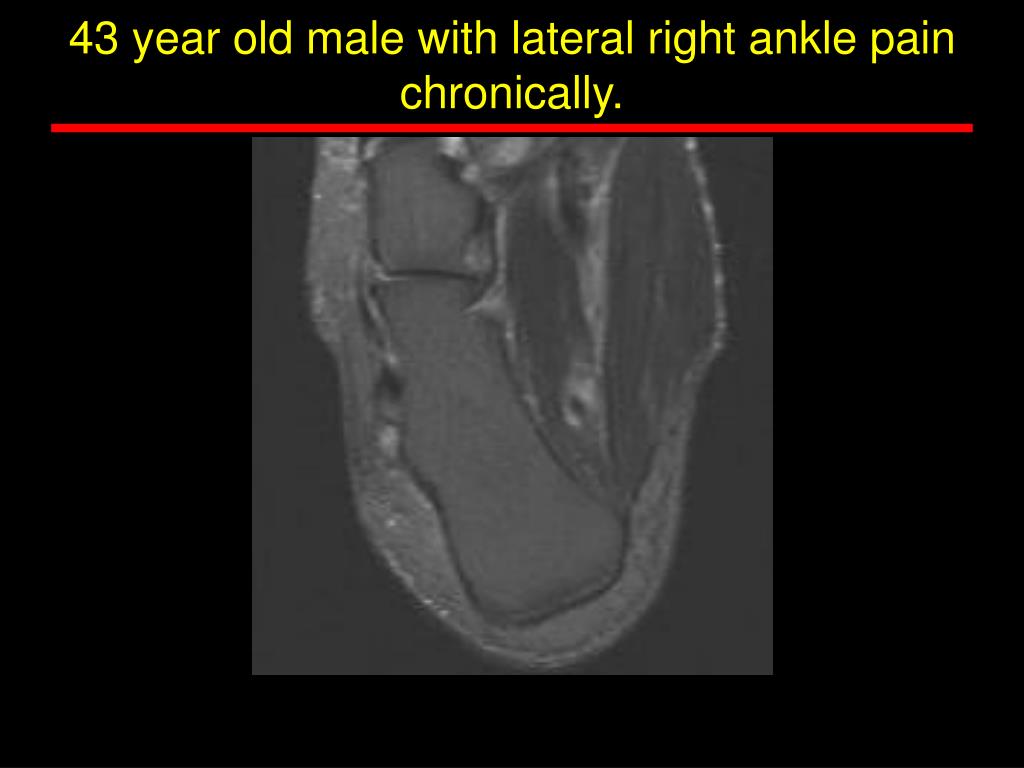

15. Herman Wu • 43 year old male with lateral right ankle pain chronically.

16. 43 year old male with lateral right ankle pain chronically.

33. Accessory ankle muscle and tendon